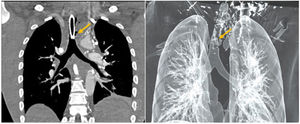

This is the case of a 26-year-old man with upper airway obstruction due to the presence of left anterior cervical mass caused by a diffuse large B-cell lymphoma. Chemotherapy and radiotherapy are started. However, due to the patient’s poor clinical course, a tracheostomy is performed. A new episode of airway obstruction occurs one week later as seen on the video-bronchoscopy (Fig. 1) with tracheal lumen infiltration (blue asterisk) due to mediastinal mass (red asterisk), prolapsed tracheal cartilage (yellow arrow), and a 5 cm fistula on the left wall. Both the distal trachea and the main carina appear normal. The CT scan performed (Fig. 2A) reveals the presence of a destructured trachea (yellow arrow) as in the 3D reconstruction (Fig. 2B).